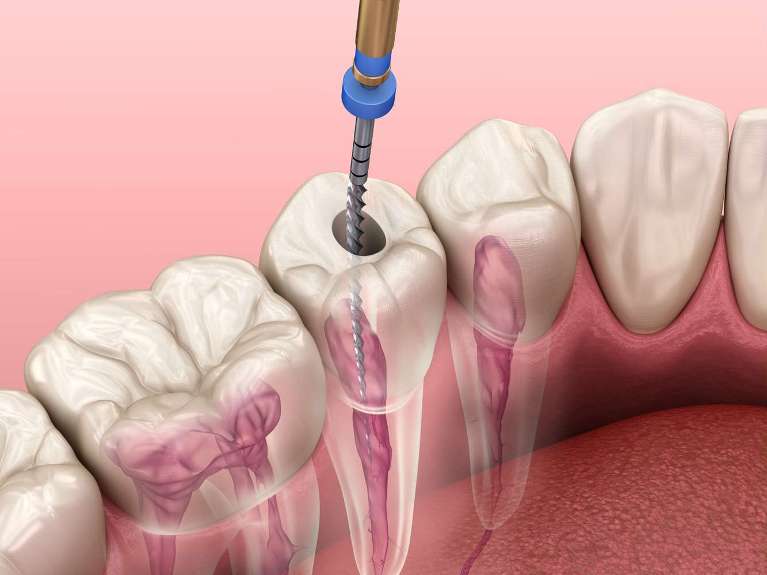

Root Canals

Modern root canal technology has significantly advanced, leading to more efficient, precise, and comfortable procedures. Key advancements include digital imaging, 3D imaging, electronic apex locators, rotary instruments, and dental lasers, all contributing to reduced treatment times and improved outcomes.